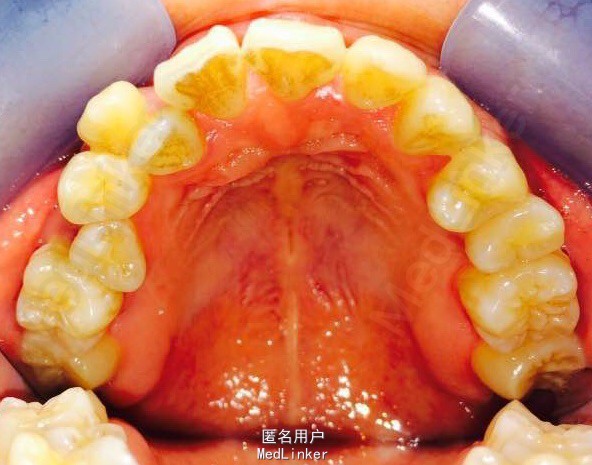

女,23岁,重度侵袭性牙周病,有家族遗传性

讨论:牙周治疗处于维护稳定阶段,下合2—2牙槽骨吸收至根尖1/3水平,是否适合正畸?下个前牙的保留问题